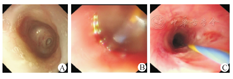

55例单纯胃镜直视下球囊扩张患儿取得了良好的治疗效果(图2),平均扩张次数为3~5次/人,其中食管闭锁术后食管狭窄43例,共扩张171次,扩张次数为(3.51±0.92)次/人,术后1例出现食管破裂,经保守治疗后好转;腐蚀性食管狭窄12例,共扩张58次,扩张次数为(4.32±0.84)次/人(表1)。

35例腐蚀性食管狭窄患儿进行了球囊扩张联合食管黏膜下注射丝裂霉素C治疗,其中男17例,女18例,年龄为(3.00±0.55)岁,均为节段性狭窄,狭窄段内径为1~4 mm,狭窄段长度为20~40 mm。25例好转,10例术后出现再狭窄,进行了支架置入治疗。患儿共注射52次,注射次数为(1.62±0.83)次/人。药物注射3次10例,注射2次20例,注射1次5例。术后无食管破裂、穿孔、出血、纵隔感染等并发症发生(图3)。

食管支架置入25例,其中10例为球囊扩张联合食管黏膜下药物注射治疗后效果欠佳,另15例患儿狭窄段较长,直接支架置入治疗(图4)。25例患儿中,食管闭锁术后狭窄患儿9例,共置入支架13次,次数为(1.22±0.31)次/人;腐蚀性食管狭窄患儿16例,共置入支架32次,次数为(2.41±0.72)次/人(表2)。15例未经过球囊扩张联合黏膜下药物注射治疗的患儿中,2例为食管闭锁术后吻合口狭窄,13例为腐蚀性食管狭窄。